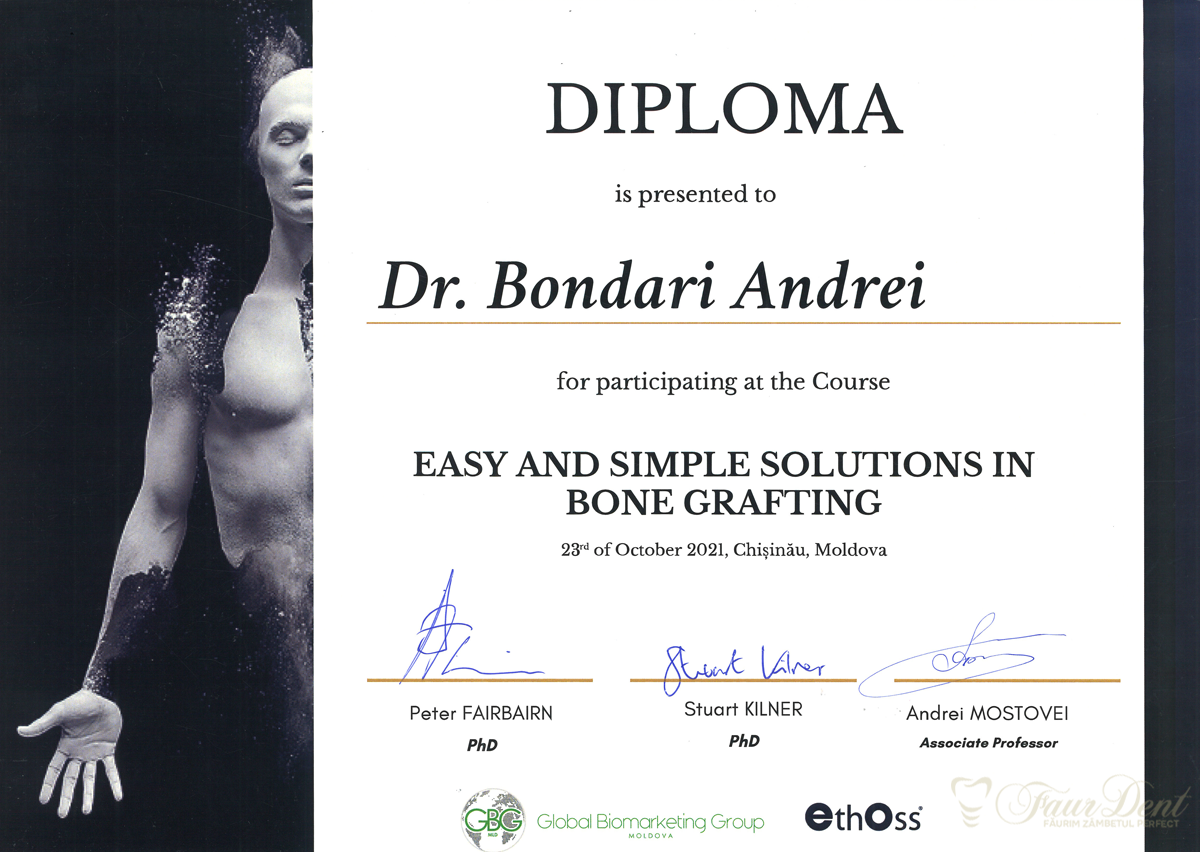

Echipa de medici ai Clinicii FaurDent